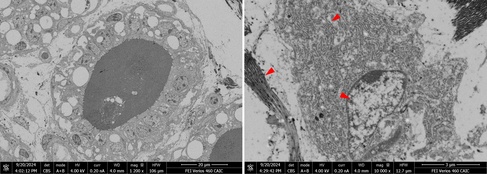

An adult, smooth-haired dachshund had to be euthanized after presenting with neurological symptoms of increasing severity and not responding to various treatment regimes. Symptoms and treatment history were suggestive of a degenerative/lysosomal storage disease and post-mortem histology indeed found intracytoplasmic, granular material particularly in neurons of the hypothalamus and thalamus.

Haematoxylin/Eosin (left) and periodic acid-Schiff stains revealing intracytoplasmic, PAS-positive brown granular deposits (green arrows) in neurons of the thalamus (Dick White Referrals).

Formalin-fixed tissue was subsequently submitted to CAIC for EM analysis. SEM blockface imaging was able to quickly localize granular deposits even in large tissue sections. Electron-dense lipofuscin granules of varying sizes were found along with lipid droplets and electron-lucent material. The electron microscopic findings supported a diagnosis of neuronal ceroid lipofuscinosis (NCL).